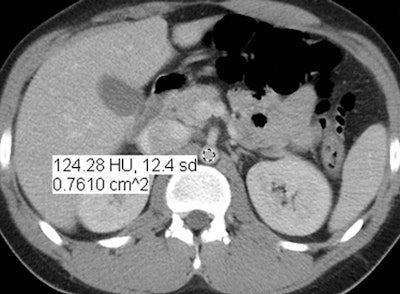

Images are of a 17-year-old boy with a history of Hodgkin's disease. Reduced-dose MBIR image (above), reduced-dose 100% ASIR image (below), reduced-dose filtered back projection image (third from top), and comparison standard-dose 30% ASIR image (bottom), all with a region of interest in the abdominal aorta for objective noise measurement. The reduced-dose MBIR image has significantly less noise compared with other reduced-dose and standard-dose reconstructions. Images republished with permission of RSNA from 10.1148/radiol.13130362, October 3, 2013.

In an objective evaluation, reduced-dose MBIR images had decreased image noise compared with standard-dose 30% ASIR images (for example, 12.7 HU versus 19.4 HU in the aorta, respectively, and 8.7 HU versus 14.2 HU in the liver).